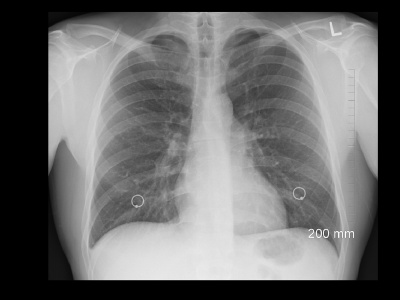

Idiopatyczne włóknienie płuc (IPF, idiopathic pulmonary fibrosis) to rzadka, przewlekła i postępująca choroba płuc, która prowadzi do stopniowego upośledzenia oddychania. Choć brzmi skomplikowanie, warto zrozumieć jej istotę – zwłaszcza że wczesna diagnoza i odpowiednie leczenie mogą realnie wpłynąć...